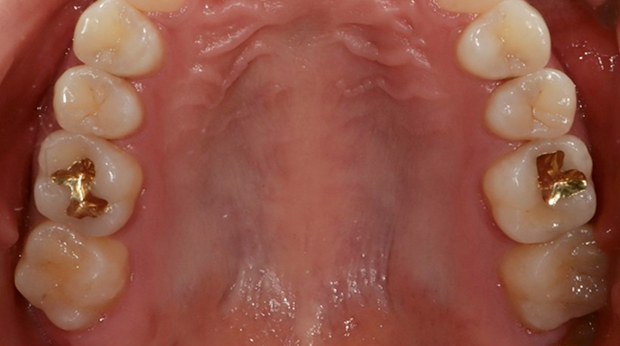

라미네이트